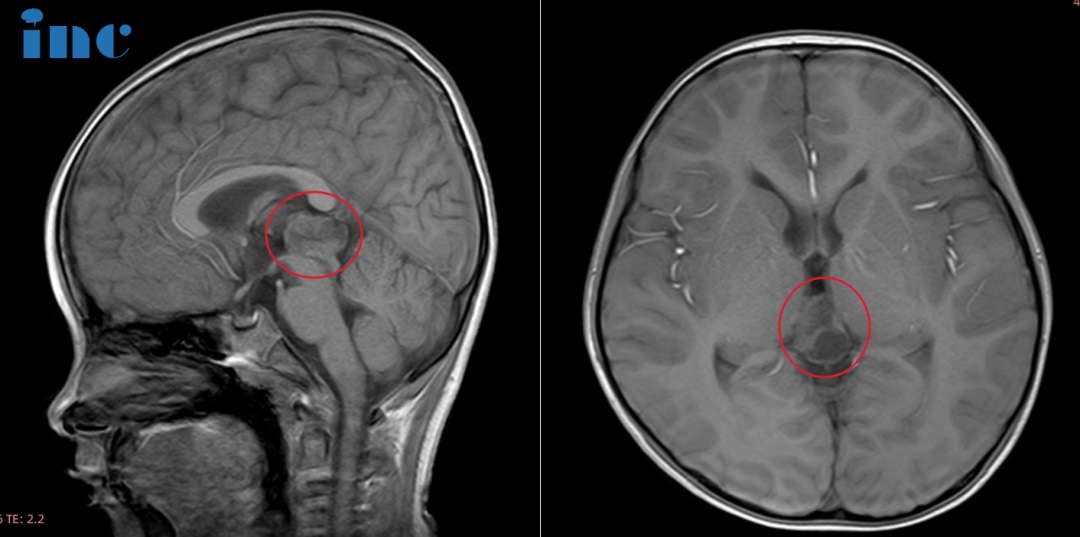

6岁男孩——松果体占位性病变

“尽快手术处理,不要给肿瘤更多时间生长得更大”

6岁的鑫鑫,2021年由于意外摔破头皮就诊,CT检查后居然发现松果体区阴影和部分钙化灶,进一步进行MRI检查后,发现22*14*17mm病灶。鑫鑫父母回想此前孩子确实有身高发育缓慢,偶尔走路不稳易绊倒等情况。2023年7月MRI结果提示病灶大小:25*19*15mm。患儿的状态并不太好,睡眠不稳、逻辑理解能力较差、记忆力也出现问题以及系列心理上的问题……孩子还小,成长的道路还很长,鑫鑫父母希望能给孩子找到更好的治疗,早日解决孩子的这些问题。

在巴教授9月来华时,这位父亲选择见一见巴教授,想要听听他的意见。巴教授在仔细研究了鑫鑫的影像资料后,建议还是尽快手术处理,不要给肿瘤更多时间生长得更大。孩子现在是6岁,如果现在手术,术后的两年孩子可以恢复,他的激素水平也可以恢复,到了8岁以后可能完全恢复好了。他们申请到了巴教授天坛医院交流手术的名额,提前入住天坛医院,等待巴教授的到来。

10月30日,巴教授抵达天坛医院后,来到病房查看鑫鑫的情况。此时的鑫鑫在父母的陪伴下在病房开心玩耍。亲切、和蔼,面对患儿始终怀着一颗童心。查体时,巴教授耐心细致地检查,哄着小患儿,“我可以摸摸你的头吗?”,巴教授检查鑫鑫的头部,并让他抬头看一看……查看好孩子身体详细情况后,面对如此可爱的鑫鑫,巴教授也为他加油打气,"Very good!"